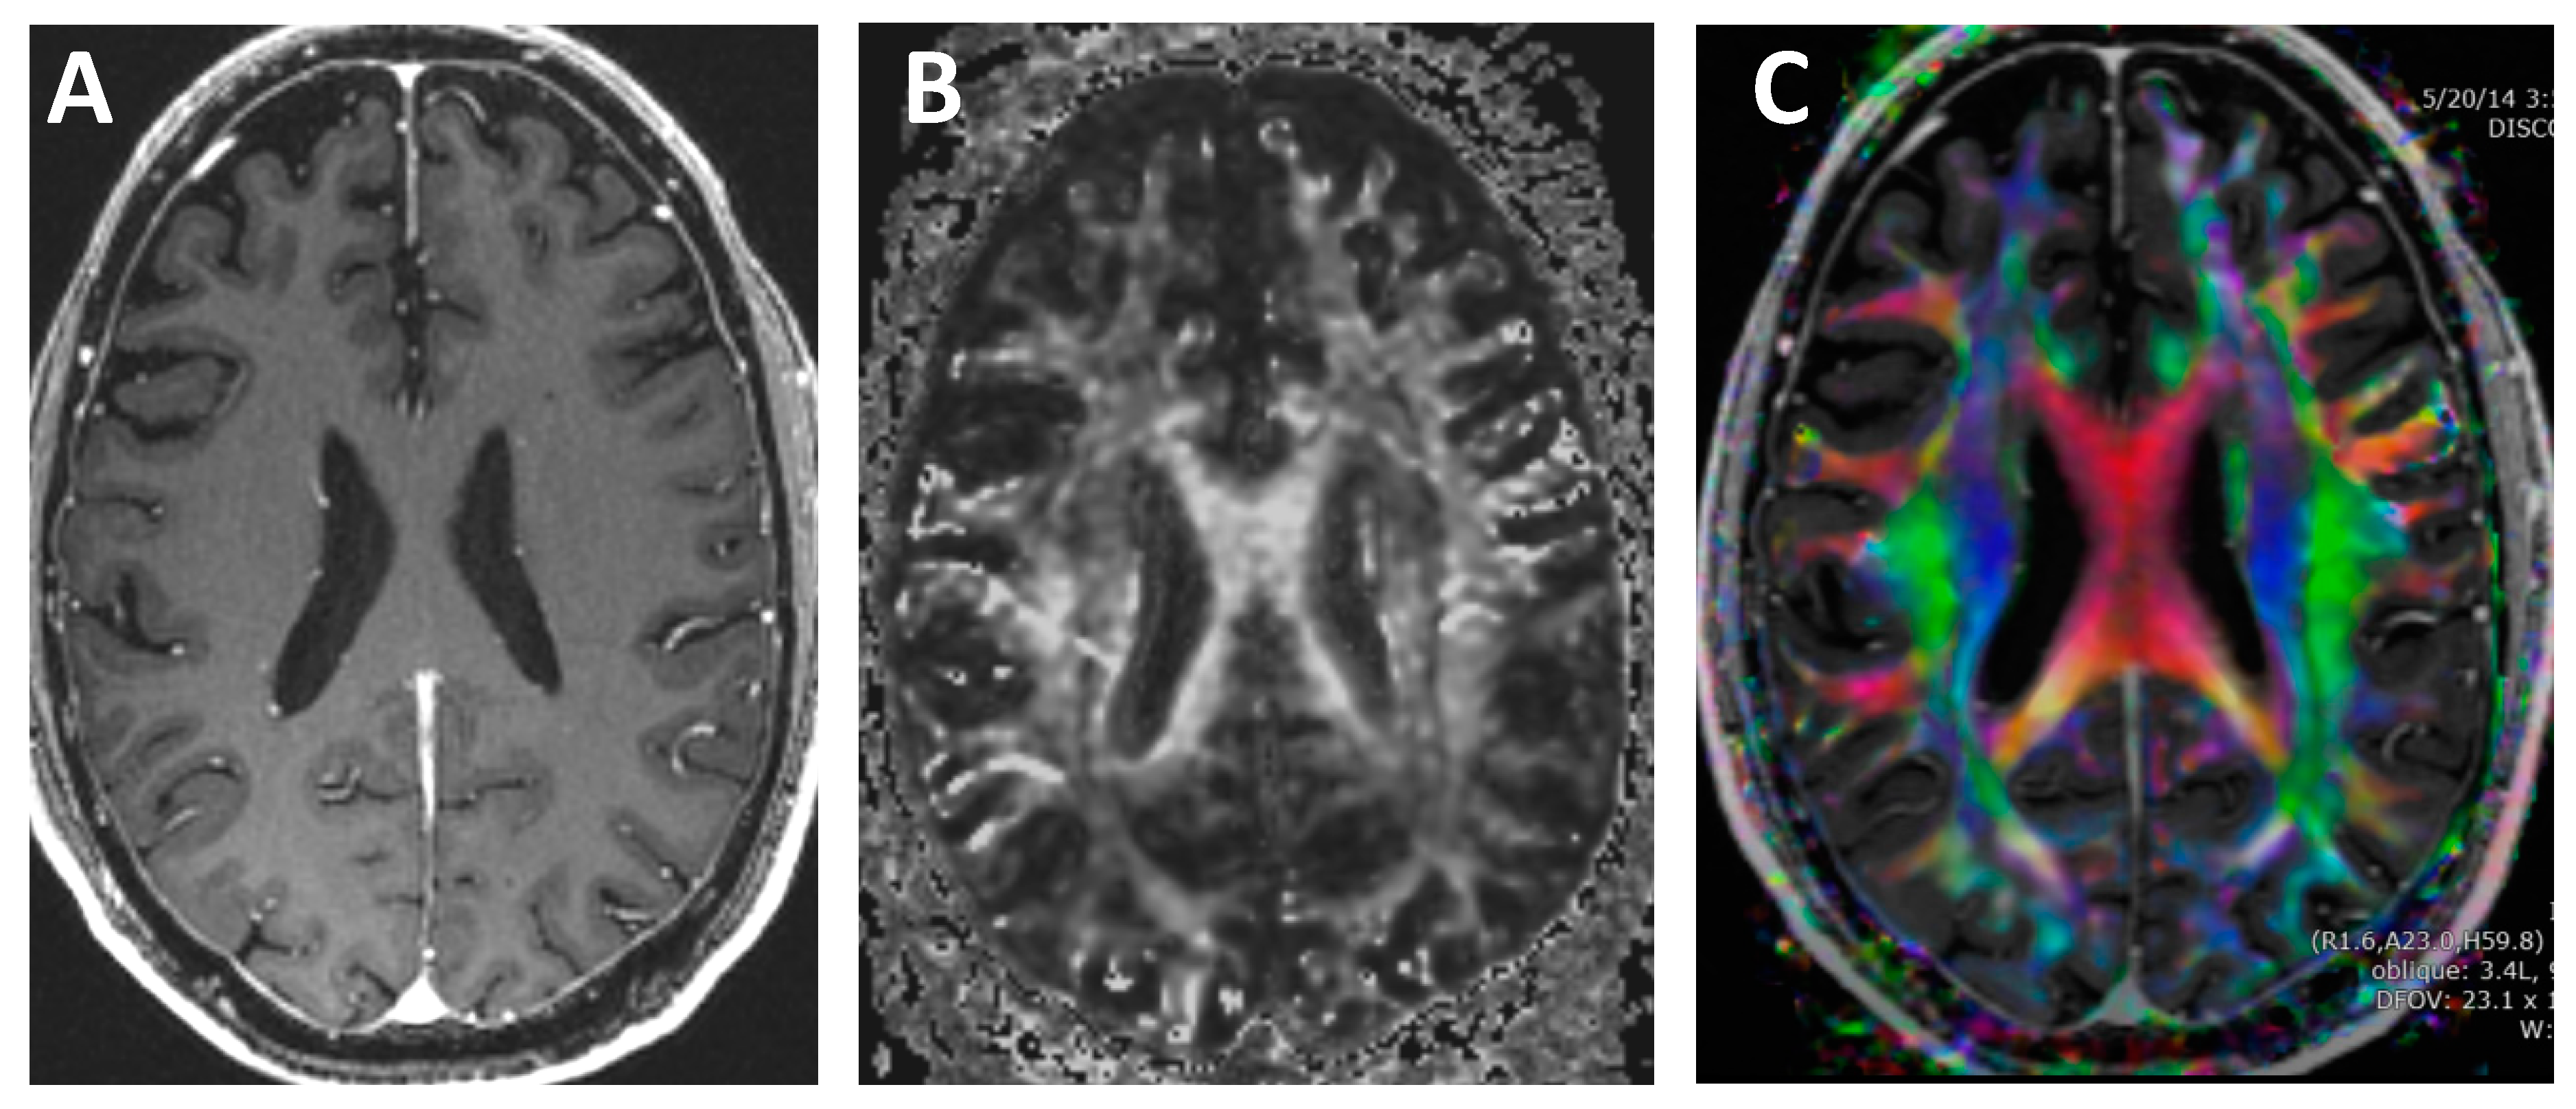

Conventional MRI imaging techniques do not provide information on the direction of the white matter tracts. In contrast, DTI quantifies both the asymmetry and the amount of water diffusion and displays this information on color-coded maps [,,,,,,,,,], see Figure 8. The concept of diffusion can be thought of as an ink drop falling onto a piece of wood. The rate of growth will be fastest in the direction along with the grains of the wood. Likewise, water diffusion is axons is directionally dependent.

Figure 8.

T1-weighted and diffusion tensor imaging (DTI). (A) Contrast-enhanced T1-weighted image. Note that the white matter is all the exact same grayscale and the direction of each white matter tract cannot be discerned. (B) Grayscale DTI anisotropy map for one diffusion-sensitizing gradient. Note that there are varying grayscales within the white matter, which correspond to the amount of diffusion signal for the particular directional diffusion-sensitizing gradient applied during the acquisition. (C) Color DTI anisotropy map overlaid onto a T1 post-contrast image. The Color DTI anisotropy is based on the composite of multiple diffusion-sensitizing gradient images. Note that there are multiple colors within the white matter map with red indicating transverse direction, blue indicating superior–inferior direction and green indicating anterior-posterior direction.